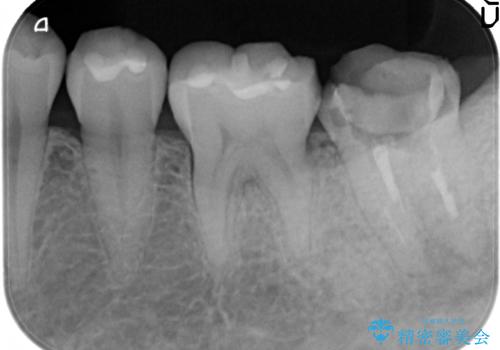

- 左下の一番奥の歯が時折激しく痛むので診て欲しいといらっしゃった方の症例です。以前に他院を受診したところ、そもそも被せ物を入れるスペースがないため抜歯しかないと言われたとのことでした。

診査の結果根尖病変を認めたため再根管治療を行った後に、被せ物を入れるスペースを作るため歯冠延長術を行いました。

歯冠延長術について

歯冠長延長術とは歯肉弁根尖側移動術とも言い、歯の高さが低くクラウン(被せ物)による治療が難しい場合に、歯茎を歯根方向に下げることで歯の高さを確保する手術です。歯の高さが十分にあることで、外れにくいしっかりとしたクラウンを被せることができます。